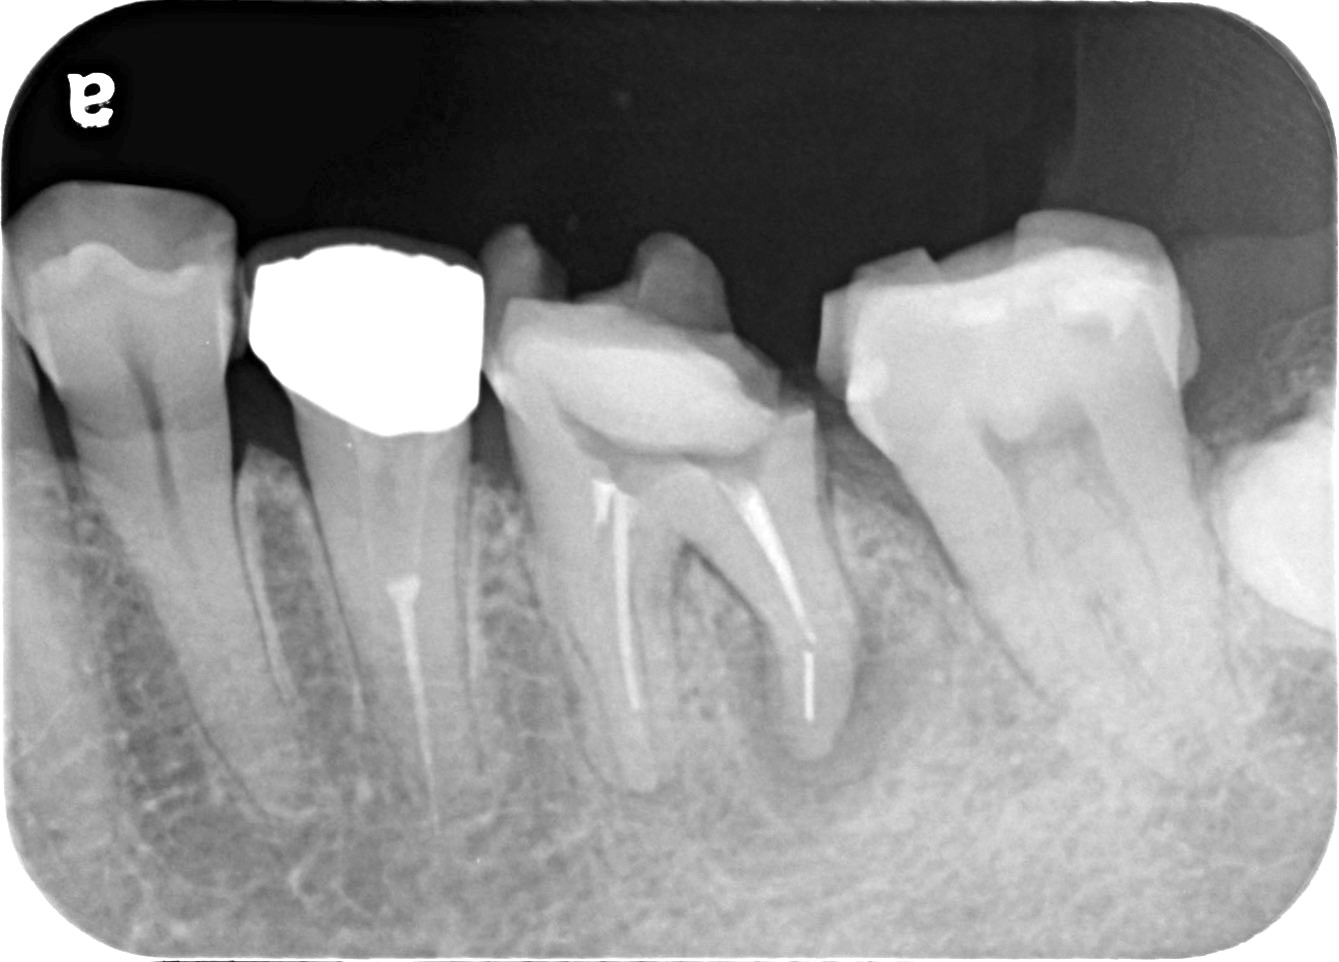

こちらは、同じ部位をCTとレントゲンで撮影したものを比較した画像です。

• 比較

左側はCT画像、右側はレントゲン画像です。赤丸で示した部分に黒い影が確認できますが、これが炎症の起きている部位です。

CTでは確認できますが、レントゲンでは写らず、見落とされることがあります。

レントゲンのみで診断した場合、この炎症に気付かないまま進行し、結果として抜歯に至るケースもあります。

当院ではそのリスクを避けるため、CTによる診断を徹底しています。